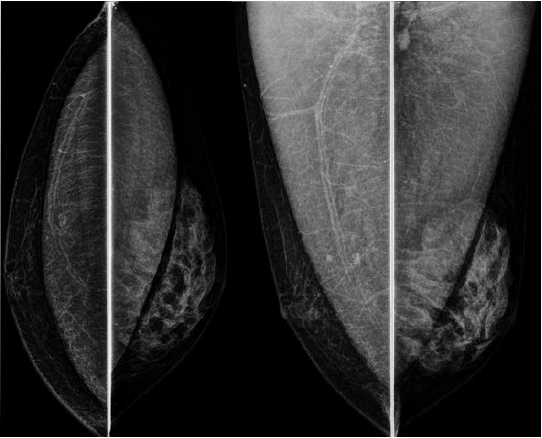

Paciente de 40 anos realizou esta mamografia para rastreio, sendo assintomática. A ultrassonografia realizada em outro serviço, 6 meses antes da mamografia, demonstrou pequeno nódulo hipoecoico de 1,5 cm no QSE da mama direita e nenhuma lesão na mama esquerda. Assinale a alternativa correspondente à hipótese diagnóstica da imagem nodular da mama esquerda observada na mamografia.

Assinale a alternativa que apresenta corretamente o que observa-se na análise das imagens da mamografia.

Uma paciente de 46 anos realizou esta mamografia.

Assinale a alternativa que contém a descrição e a classificação BIRADS correspondente.